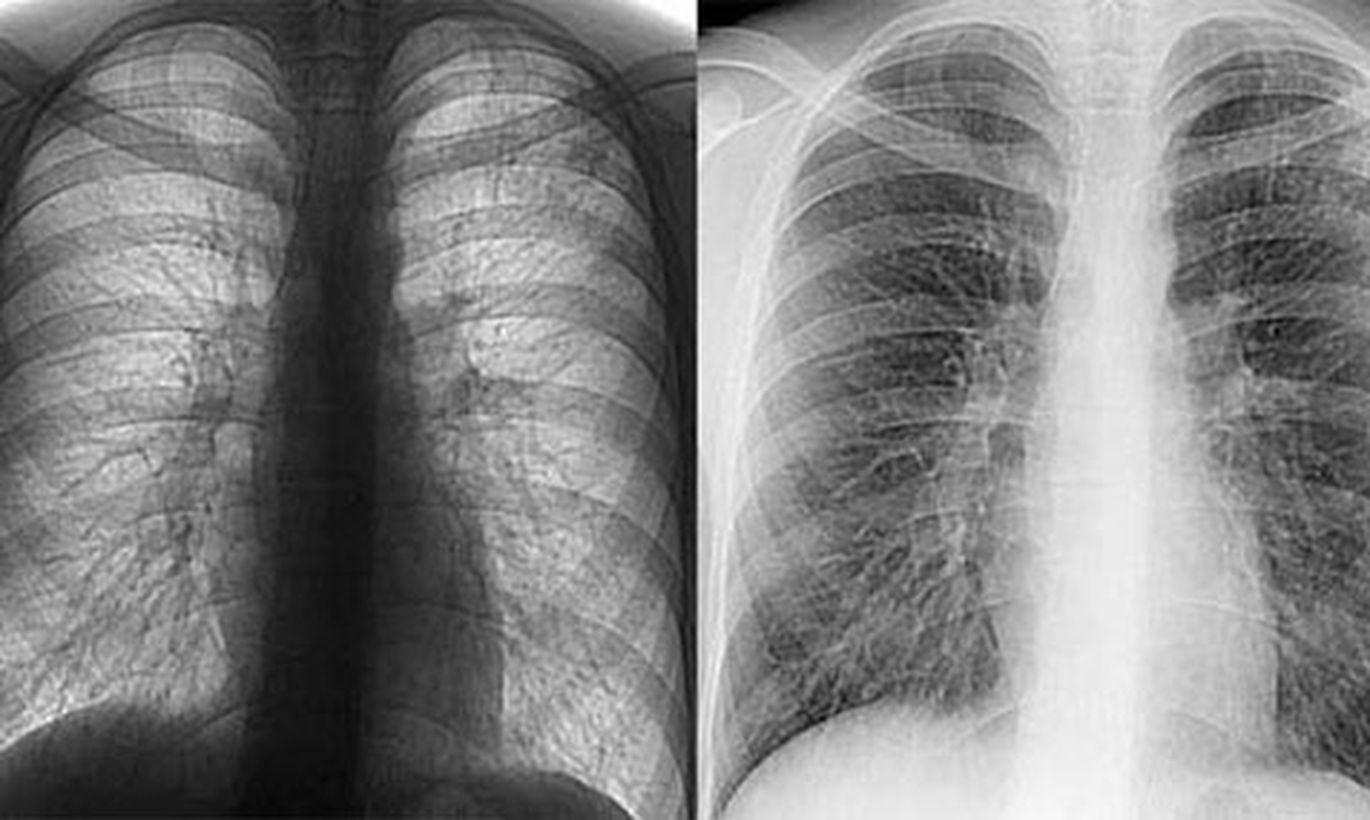

Очаговый туберкулез рентген

Рентген грудной клетки туберкулез

Диссеминированный туберкулез на рентгенограмме